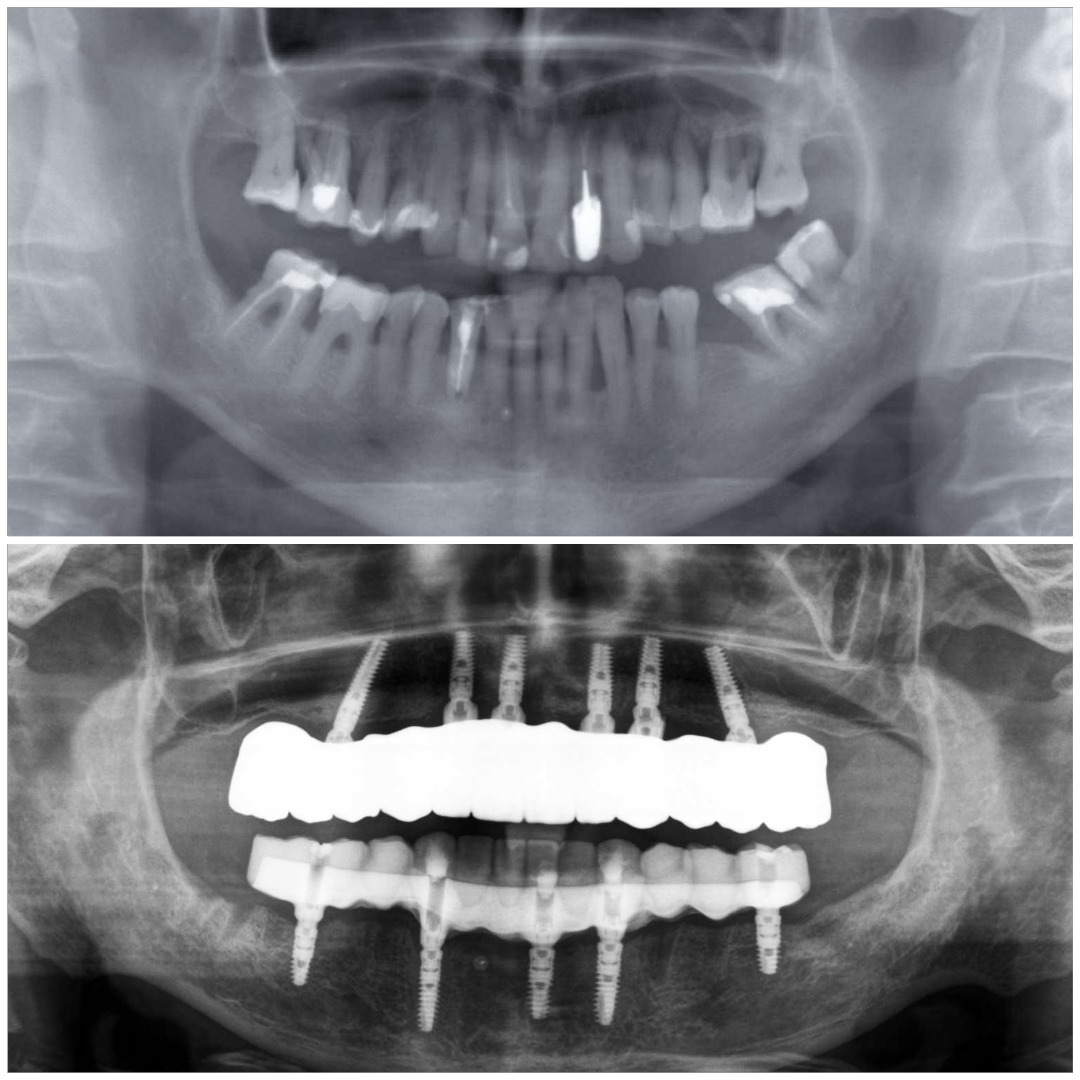

Przypadek 1

Pacjent zgłosił się z powodu licznych problemów z zębami oraz dolegliwości bólowych głowy. Zęby z powodu znacznej ruchomości nie stanowiły odpowiedniej podpory podczas żucia. Niestety wieloletniej terapia periodontologiczna choroby przyzębia nie przynosiła efektów. Zęby zostały zakwalifikowane do usunięcia. Nowy zgryz został odtworzony i oparty na 6 implantach w szczęce oraz 5 w żuchwie. Informacje z badania stawowe "kondylografii" pomogły zaplanować nowe prawidłowe zwarcie. Poza wyleczeniem dolegliwośći bólowych głowy oraz przywróceniu komfortu żucia i uśmiechu, Pacjent po zakończonej terapii zgłasza znaczne ograniczenie chrapania.

leczenie zaplanował oraz przeprowadził lek. dent Kamil Kikowicz